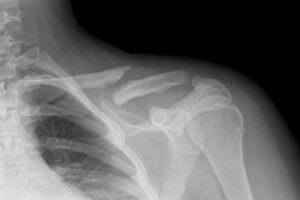

Врачи отмечают, что перелом плеча со смещением является серьезной травмой, требующей внимательного подхода к диагностике и лечению. Специалисты подчеркивают важность своевременного обращения за медицинской помощью, так как неправильное или запоздалое лечение может привести к осложнениям, таким как неправильное сращение костей или ограничение подвижности. Врачи рекомендуют проводить рентгенографию для точной оценки состояния кости и степени смещения. В большинстве случаев требуется хирургическое вмешательство для восстановления правильного положения костей. Реабилитация после операции также играет ключевую роль в восстановлении функции плеча, и врачи советуют пациентам следовать рекомендациям по физической терапии для достижения наилучших результатов.

Лечение травмы начинается с обезболивания и обследования с помощью рентгена. Чтобы получить полную картину состояния сустава, степени смещения, делаются снимки нескольких проекций.

Через 4 месяца делается рентген — снимок, и, в случае сращивания костной ткани, фиксирующие элементы удаляются. Но в отдельных случаях у людей пожилого возраста фиксаторы могут оставить стационарно, с периодическим рентген — контролем.